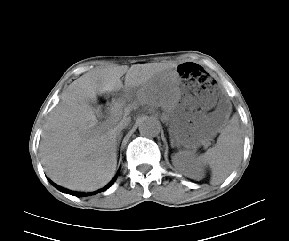

标题: CT19533:病变来源于哪?

患者,男,发现上腹部包块两月余。

病变位于肝胃间隙,实际就是位于小网膜囊(左肝下后间隙),呈轻度不均匀性强化,腹腔内及腹膜后见多发肿大淋巴结。所以我考虑肝胃间隙恶性胃肠间质瘤并淋巴结转移。

病灶强化不显著,灶周及腹膜后见多量淋巴结肿大,考虑淋巴瘤可能,其次考虑间质瘤

病灶与胰腺分界不清,来源于胰腺?

强化后病变与胃壁分界清楚,并且血供不是来源胃壁血管。考虑胰腺颈体癌并腹腔腹膜后淋巴结转移。